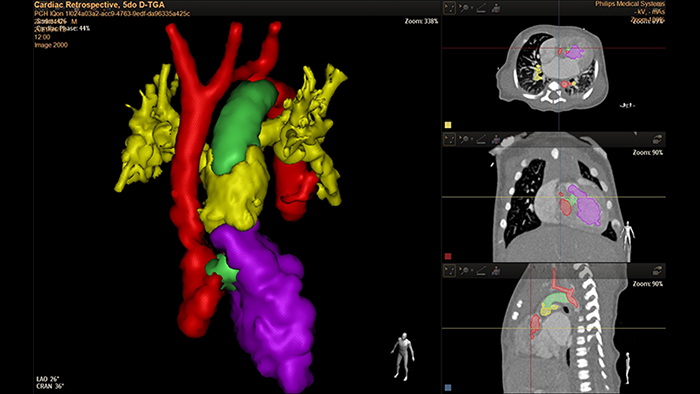

5-day old D-TGA analysis with HeartNavigator